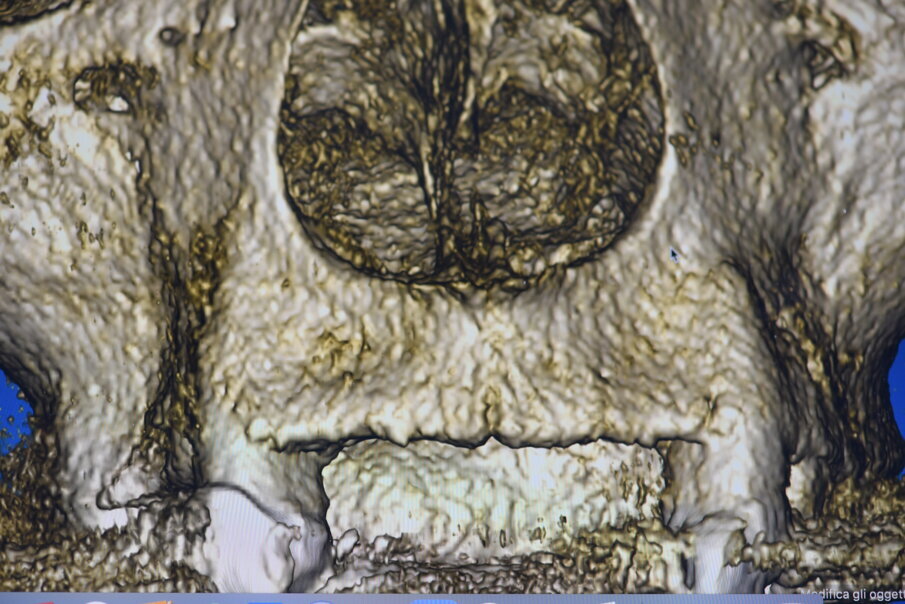

Fig. 8_Impatto visivo della CBCT nella porzione vestibolare che evidenzia la marcata lacuna ossea che impatta sull’estetica del II° sestante.

La CBCT ha riscontrato un deficit del volume osseo nella porzione vestibolare (Fig. 8), pur mantenendo la possibilità di alloggiare gli impianti in osso nativo e rigenerando la parte vestibolare nell’intento di dar maggior supporto al labbro, in sostituzione della flangia di resina del precedente provvisorio. La dima chirurgica progettata in previsione di un intervento a lembo aperto viene stabilizzata dai diversi monconi presenti sull’arcata preparati evitando sottosquadri e angoli vivi che renderebbero difficoltosa la stabilità della dima nell’atto chirurgico. È altresì importante che gli elementi residui non presentino mobilità al fine di limitarne la precisione (Fig. 18). Nel caso di appoggio ai denti naturali della dima chirurgica è necessario che abbia dei fori in corrispondenza degli elementi così da valutare il corretto posizionamento stessa durante l’intero intervento (Figg. 19, 20). In caso di zone estetiche siamo soliti dare prevalenza all’uso di impianti in Zirconia bifasici (Fig. 21). Gli impianti in Zirconia rappresentano un vantaggio in zone estetiche per il loro caratteristico colore oltre che per la particolare biocompatibilità, è infatti ormai noto la formazione di un creaping epiteliale che favorisce una maggior adesione emodesmosomiale con una stabilità del tessuto connettivo perimplantare migliore rispetto al titanio. L’impianto scelto è un impianto bifasico tissue level a connessione interna che presenta un trattamento di superficie tale da renderlo idrofilo, cioè aumenta la bagnabilità di superficie e conseguentemente ne aumenta la prestazione riducendo i tempi di guarigione ossea primaria (Fig. 22).